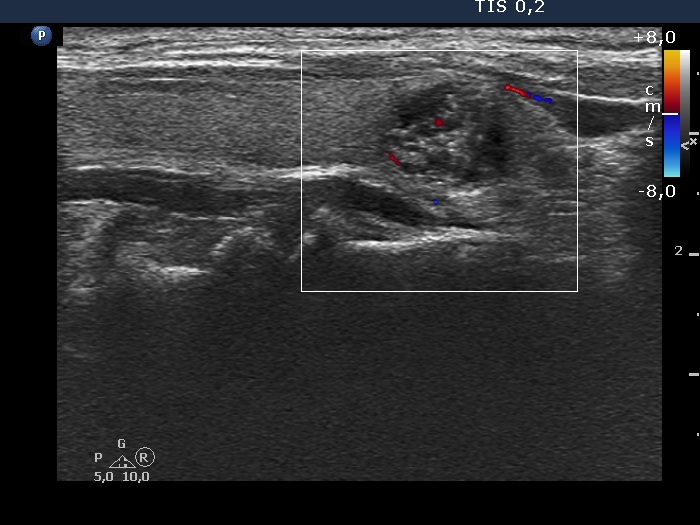

Extrathyroidal spread - case 2166 (ultrasonographic picture 8)

Right lobe, longitudinal scan, color Doppler mode. The vascularization is not specific.